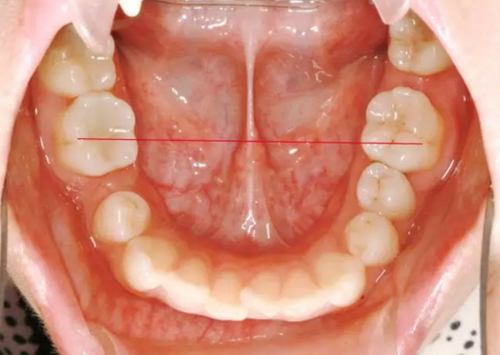

正畸醫(yī)生都想把患者做到“理想頜”,而臨床工作中卻很難如愿;這個(gè)患者到診時(shí),口內(nèi)已經(jīng)有兩顆恒牙缺失;

37,45缺失后,鄰牙近中移動(dòng)占據(jù)了部分牙位;患者要求減少治療費(fèi)用,不做種植修復(fù),那怎么協(xié)調(diào)右側(cè)的咬合關(guān)系?

15是根管治療過(guò)的牙齒,只好忍痛舍去......

在滿足功能的前提下,退而求其次...有時(shí)候,正畸醫(yī)生不得不妥協(xié)。